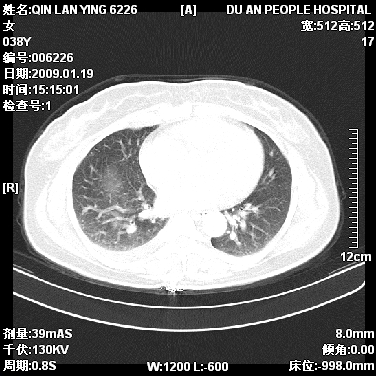

女,38岁,胸疼1个月。wbc:1万4

考虑----右肺中心型肺癌---阻塞性肺炎-----纵膈淋巴结及胸膜转移----肝脏转移

1)右肺中央型肺癌并右肺上叶阻塞性肺炎、节段性肺不张,纵隔淋巴结转移、右侧胸膜转移、肝脏转移。2)右侧胸腔少量积液。

1、右侧中央型肺癌并阻塞性肺不张,纵隔内、主动脉弓旁、右肺门淋巴结及肝脏转移可能性大,建议纤支镜进一步检查。

2、右侧胸腔积液。

本病例有几个容易诊断的地方:1、右肺上叶前段支气管闭塞,肺不张。2、淋巴结明显肿大。3、肝脏多个类圆形低密度影呈“牛眼征”改变,高度提示转移。

从影像学角度分析      右肺上叶中央型肺癌,并阻塞性不张、肺炎,纵隔淋巴结、膈顶淋巴结转移。

肝内两个大小不等低密度结节,内可见更低密度影,首先考虑肝内转移瘤,但联想到患者wbc1万4,建议楼主还是做个增强比较明确,除外肝脓肿的可能。